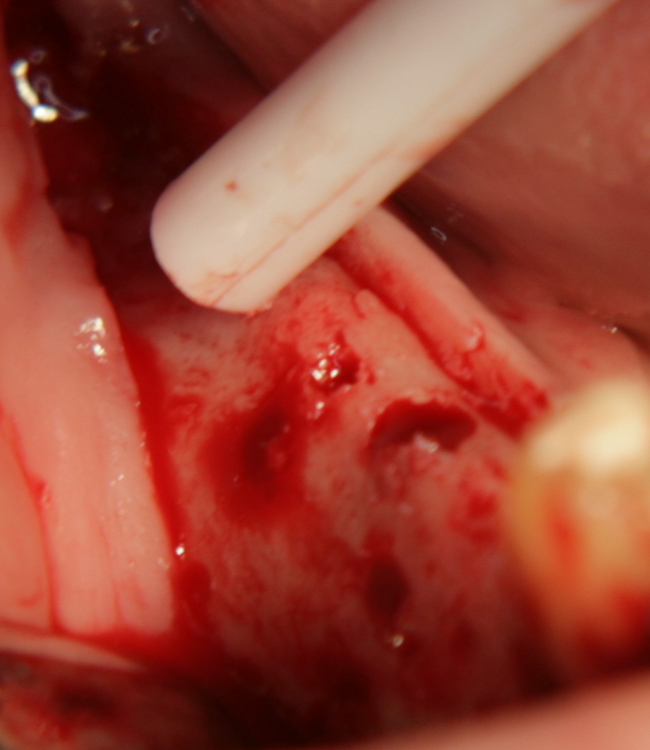

С фрезата за автогенна кост се извършва много бързо и лесно отнемане на

кортикалната кост

Автогенна кост